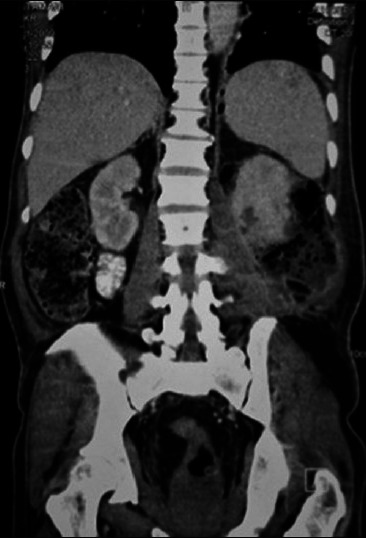

Emphysematous Pyelonephritis (EPN) is a severe, necrotizing, life threatening infection of the renal parenchyma and management is not standardised due to scarcity of literature. We present 3 patients with this rare entity. All 3 patients were of class III on CECT findings based on Huang's classification and had more than two risk factors. Our first patient underwent percutaneous drainage of his condition upon which he recovered. The second and third patients underwent a laparotomy and nephrectomy. The second patient recovered after a stormy post operative period and the third patient died. Management of the first patient was contrary to that recommended in literature, for the other two it was as per recommendations. On successful management of our first patient without surgery and seeing no discernable benefits of surgery for our other two patients, it is possible that percutaneous drainage alone, coupled with antibiotics may be a viable strategy for managing this condition with nephrectomy being considered as a second tier option.

肺气肿性肾盂肾炎(EPN)是一种严重的、坏死性的、危及生命的肾实质感染,由于缺乏文献,其治疗方法尚不规范。我们报告了3例患有这种罕见疾病的患者。根据Huang的分类,所有3例患者的CECT结果均为III级,并且有两个以上的危险因素。我们的第一个病人接受了经皮引流术,他痊愈了。第二名和第三名患者分别进行了剖腹手术和肾切除术。第二例患者术后经历了一段暴风雨期后恢复,第三例患者死亡。第一个病人的治疗方法与文献中推荐的方法相反,另外两个病人的治疗方法与文献中推荐的方法相反。我们的第一个患者成功地进行了手术治疗,而其他两名患者没有明显的手术益处,因此,单独经皮引流联合抗生素可能是治疗这种疾病的可行策略,而肾切除术被认为是第二级选择。